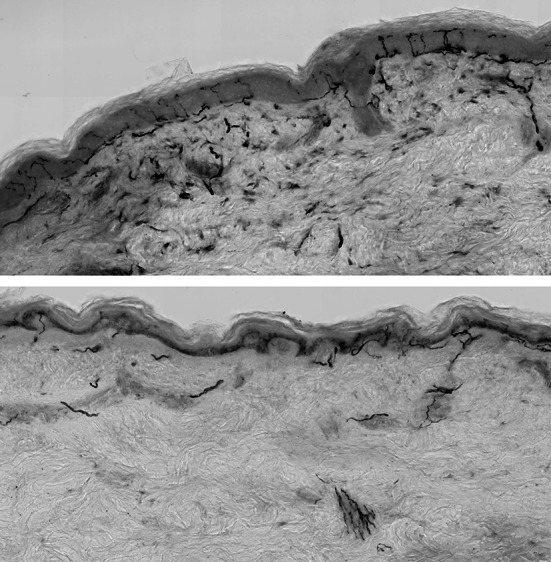

纤维肌痛综合征(FMS)在诊断和治疗方面都是一种复杂而具有挑战性的疾病,越来越多的证据表明,小纤维病理(SFP)在其病理生理中起着重要作用。SFP在FMS中的作用意义尚不清楚;然而,最近的证据表明,周围神经系统的退化和功能障碍,特别是小的无髓鞘纤维,这可能影响病理生理和潜在的表型。皮肤活检和角膜共聚焦显微镜(CCM)一致表明,约50%的FMS患者有SFP。CCM是一种非侵入性测量小神经纤维的方法,可以检测到与神经性疼痛描述符相关的小纤维损失。此外,定量感觉测试显示异常,主要是疼痛压力/机械性疼痛阈值。这篇叙述性综述提供了对FMS病理生理维度的全面理解,并明确关注小神经纤维和周围神经系统,为未来的研究提供了路线图。

Fibromyalgia syndrome (FMS) presents a complex and challenging disorder in both the diagnosis and treatment, with emerging evidence suggesting a role of small fibre pathology (SFP) in its pathophysiology. The significance of the role of SFP in FMS remains unclear; however, recent evidence suggests degeneration and dysfunction of the peripheral nervous system, particularly small unmyelinated fibres, which may influence pathophysiology and underlying phenotype. Both skin biopsy and corneal confocal microscopy (CCM) have consistently demonstrated that ~ 50% of people with FMS have SFP. CCM, a non-invasive measure of small nerve fibres has detected small fibre loss, correlating with neuropathic pain descriptors. Additionally, quantitative sensory testing has shown abnormalities, primarily in pain pressure/mechanical pain thresholds. This narrative review provides a comprehensive understanding of the pathophysiological dimensions of FMS with a clear focus on small nerve fibres and the peripheral nervous system, offering a roadmap for future research.